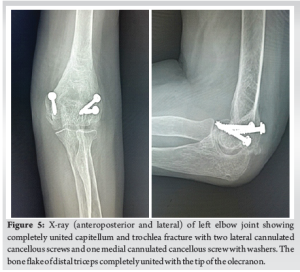

Six months after the surgery, the patient successfully regained a satisfactory range of motion in her left elbow. The comparison of the range of motion between the operated elbow and the normal elbow is illustrated in Table 2 and Fig. 4. The Mayo Elbow Performance Score recorded was 80, indicating a good outcome, while the DASH score was 17.5 at the 6-month mark. Grip strength was measured at 90% on the right side. She was able to return to her prior level of activity and could perform all her daily living activities. There was no indication of varus, valgus, or posterolateral ligamentous instability. The follow-up X-ray (Fig. 5) demonstrates a complete union of the fractures, with no signs of myositis ossificans (Figs. 4 and 5, Table 2).